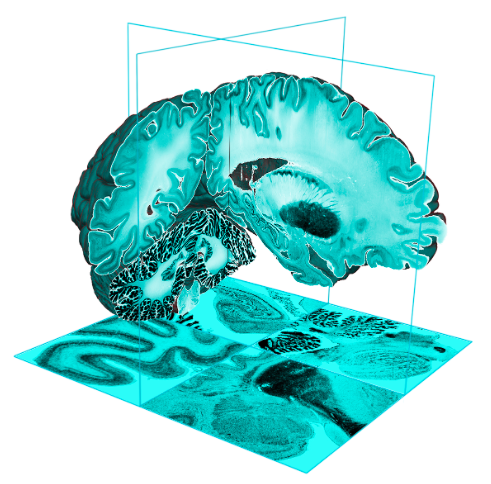

Imaging Data

2. Visualisation:

Imaging Browser, BrainBrowser3. Quality Control:

- Visualization - 3D and 4D

BrainBrowser

..a set of web-based 3D visualization tools primarily used for viewing neurological data i.e. MRI scans.

It allows for real-time manipulation and analysis of 3D neuroimaging data through any modern web browser. TRY ME!

BrainBrowser - 3D Surface Viewer